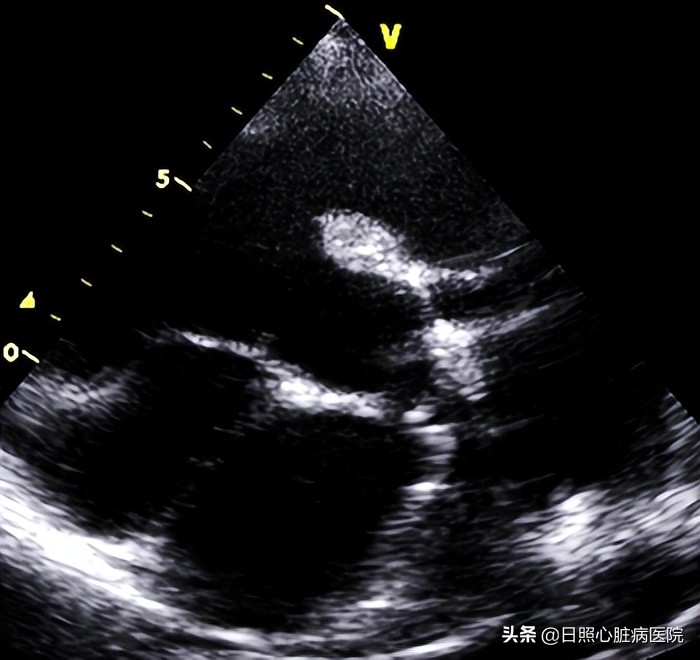

当出现室间隔缺损相关的临床表现时需要做心电图、胸部x线片检查、超声心动图检查帮助诊断。其中超声心动图是首选的检查手段,它可以精确的诊断出缺损口大小、分流及部位。

如果发现宝宝有室间隔缺损,家长先不要恐慌,室间隔缺损是治疗效果最好的先天性心脏病之一,只要及时治疗,治愈后可达到与正常人一样的效果。很多小的缺损,可以自愈,中等大小室缺,可以随访,每三个月行心脏彩超检查,对于比较大的缺损,需要及时治疗。